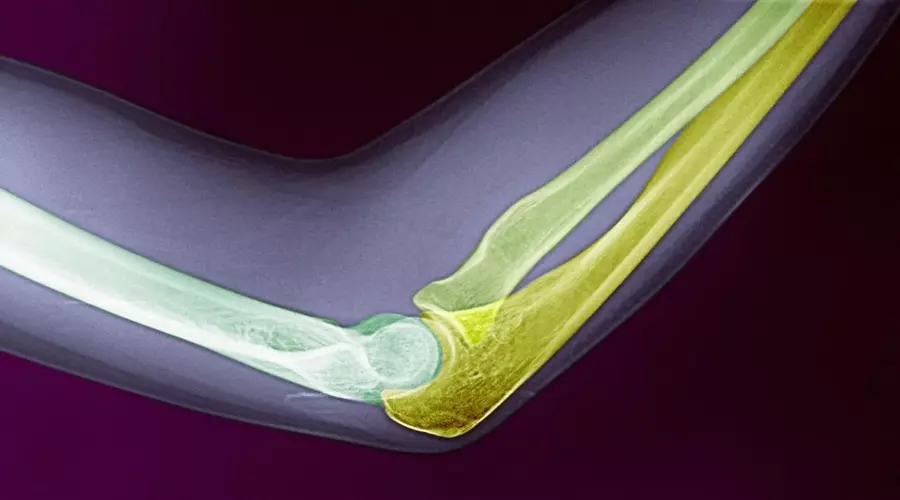

شکستگی آرنج 19 آذر 1402

• بیماری ها

• مقالات

شکستگی آرنج: انواع، علائم، تشخیص و درمان